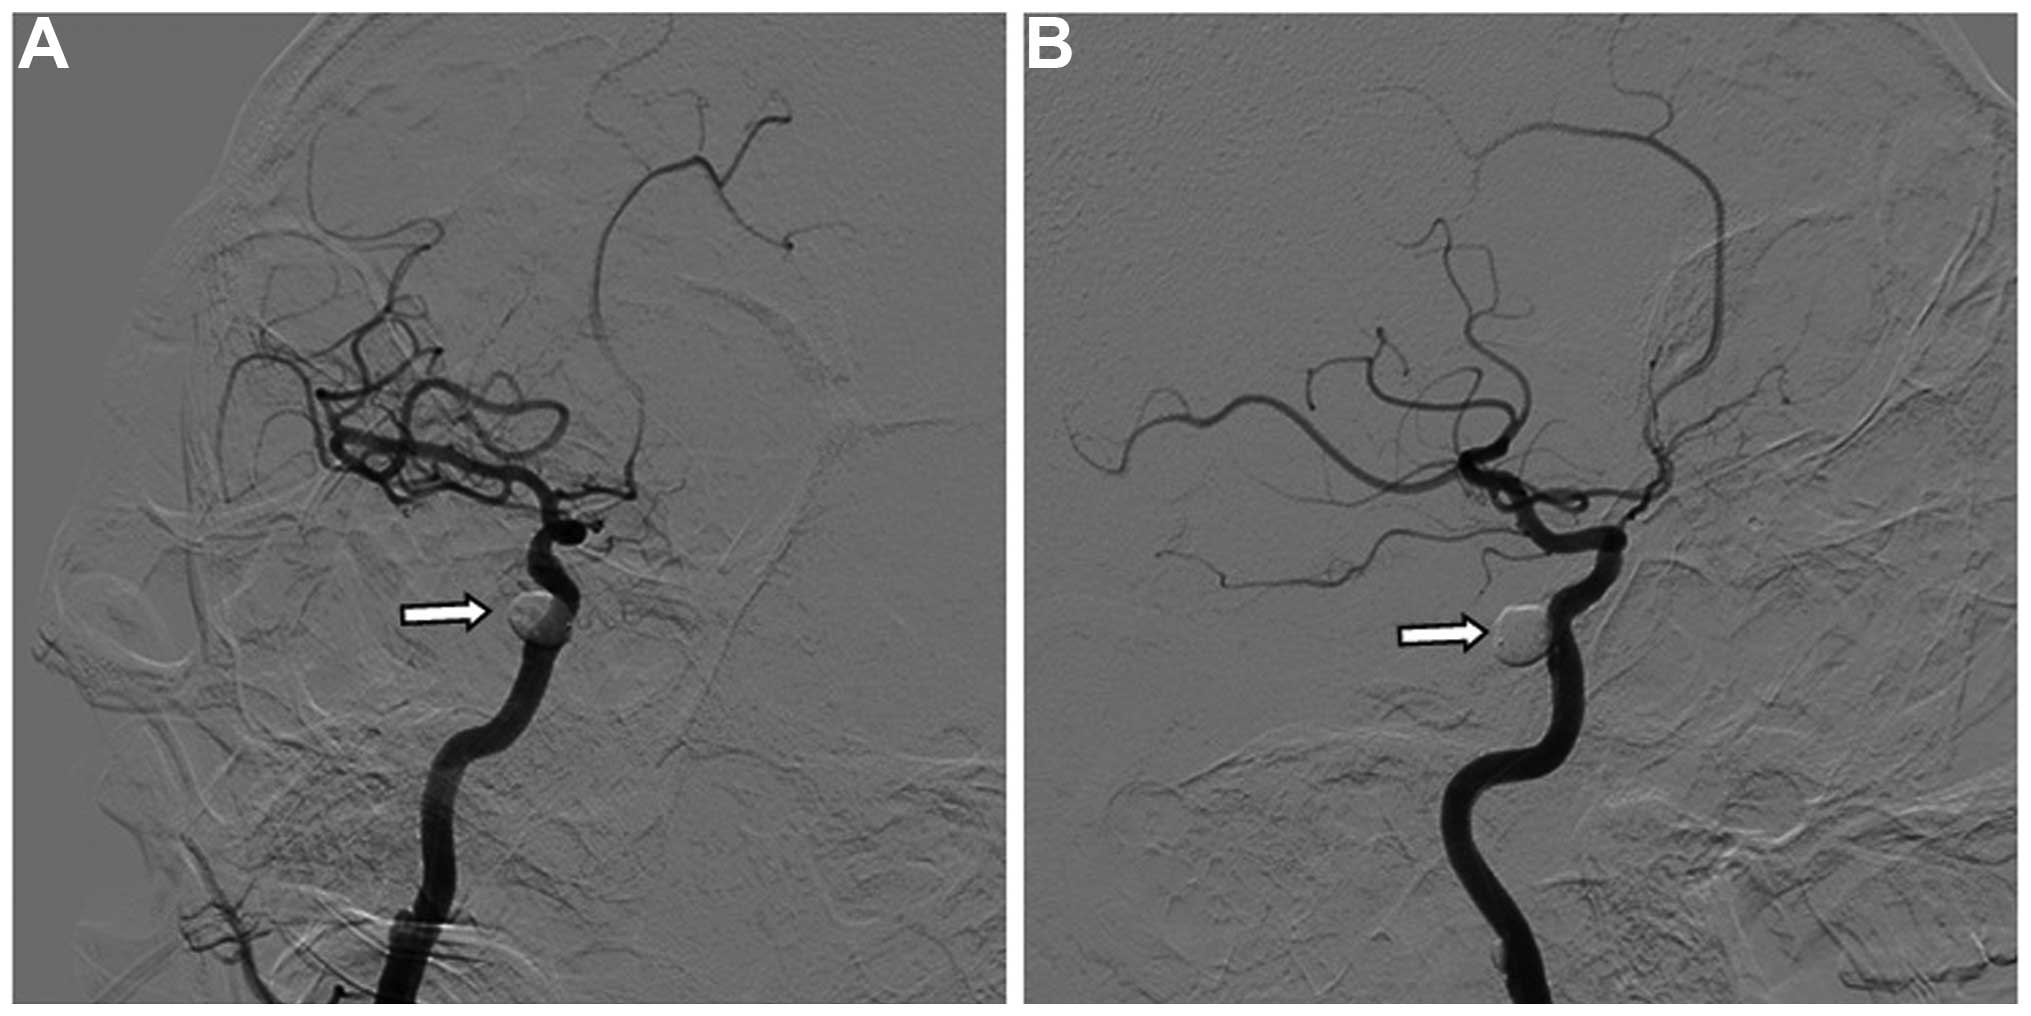

Brainstem edema caused by traumatic carotid-cavernous fistula (TCCF) is rare, and there is little information available regarding its clinical characteristics. The present report describes the case of a 51‑year‑old man with TCCF, who presented with right exophthalmos and intracranial bruit for 1 week. One month prior to admission at hospital, he fractured the frontal and ethmoid sinuses. Digital subtraction angiography confirmed the diagnosis of TCCF, and magnetic resonance imaging (MRI) suggested edema on the right side of the pons. Five days after admission, the patient exhibited left hemiparesis, and MRI revealed aggravation of the brainstem edema. Following treatment with transarterial balloon embolization, the clinical symptoms, including hemiparesis, were relieved; at the 1‑month follow‑up, the brain edema had disappeared. The patient was normal at the 6‑month follow‑up. Following the report of the present case, we reviewed six additional cases previously reported in the literature and discussed the potential mechanisms of TCCF‑associated brainstem edema. We conclude that occlusion of the superior petrosal sinus may contribute to brainstem edema caused by TCCF. Relief of the brainstem edema and brainstem edema‑associated clinical symptoms can be achieved with transarterial coil or balloon embolization of the TCCF to reduce the drainage pressure in the brainstem veins.

Figure 5